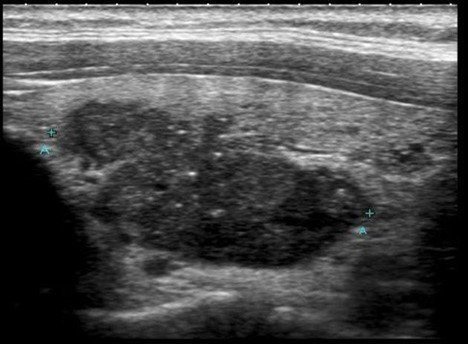

Ultrasonography Performed On 61 Year Old Female With Medullary Thyroid Download Scientific Diagram

A B Ultrasonography Of Thyroid Gland Showing Abnormal Texture With Download Scientific Diagram